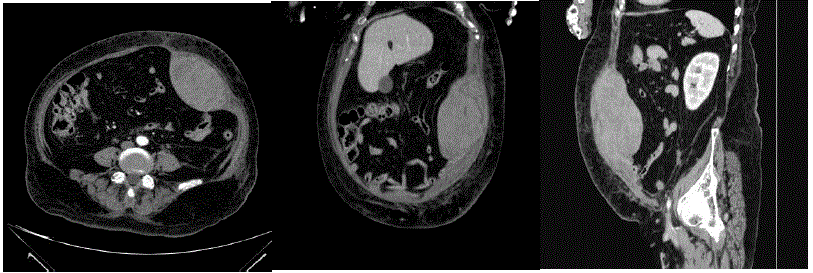

Homem, 37 anos de idade, refere dor abdominal na fossa ilíaca direita há 12 dias, acompanhada de febre de até 38ºC, perda de apetite e queda do estado geral. Procurou o serviço de urgência por duas vezes e há 6 dias foi iniciado ciprofloxacino devido à hipótese de infecção urinária. Retorna hoje ao Pronto-Socorro devido a persistência do quadro.

Ao exame clínico:

Regular estado geral, febril, FC:90 bpm, PA: 130x80 mmHg

Tórax sem alterações.

Abdome flácido, massa palpável de cerca de 10cm na fossa ilíaca e flanco direito, dor localizada na região da massa. Sem sinais de irritação peritoneal. Toque retal sem alterações.

Exames laboratoriais: Hb: 14,6 g/dL; Leuco: 26,57 mil/mm3; PCR: 324mg/dL; Creat: 1,37 mg/dl; Ureia: 51 mg/dl; demais exames normais.

Realizada tomografia de abdome (imagens a seguir):

Qual é o melhor tratamento?